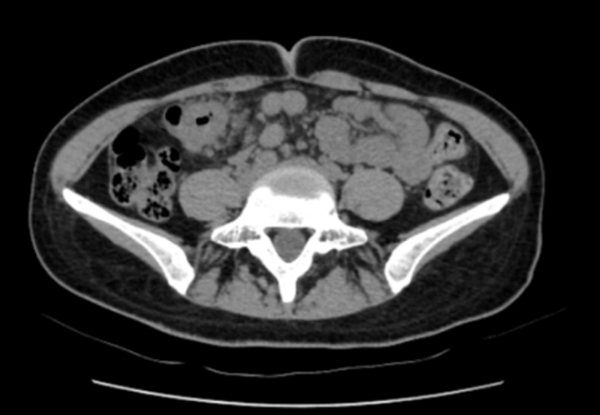

“脐周疼痛对应的多是小肠问题,右上腹的包块却指向肝胆、结肠等器官,这两者对不上。”医生立刻警觉起来,当即安排王女士做腹部CT检查。影像结果很快出来:结肠近肝曲处肠壁可疑增厚,肠腔狭窄——这个信号让诊疗团队的神经瞬间紧绷。

三天后,消化内镜中心孙舒仰医生操作的结肠镜顺利进行。当镜头探至升结肠近肝曲——正是之前查体摸到包块的位置时,一个不规则肿物赫然出现:它环绕肠腔2/3,表面糜烂溃疡还附着污苔,质地脆弱一碰就出血,肠壁已变得僵硬,管腔也出现偏心性狭窄,万幸肠镜还能勉强通过。“高度怀疑结肠癌。”孙舒仰医生当场判断。

几天后的病理报告印证了这一结论:中分化腺癌。“原来腹痛、大便不成型是肠腔狭窄导致的不完全性肠梗阻,进食后压力增大就疼,排便后缓解。”医生解释道。从首次就诊到病理确诊,全程仅用6天,这背后是消化内科、影像科、内镜中心、病理科的高效协同作战。目前,王女士已转至肿瘤科和普外科接受进一步治疗。